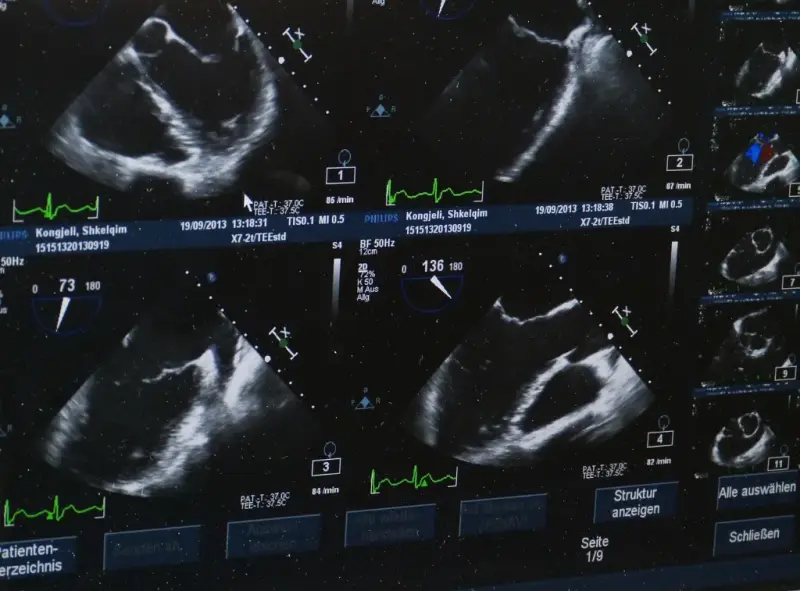

Warto również podkreślić, że w niektórych przypadkach, takich jak ocena przepływu krwi czy badania echokardiograficzne, jakość obrazu ma krytyczne znaczenie dla precyzyjnej oceny stanu pacjenta. Brak możliwości dokładnego zobrazowania przepływu krwi może prowadzić do niewłaściwej oceny stanu serca czy naczyń krwionośnych, co w konsekwencji może zagrażać zdrowiu pacjenta.

Z kolei w kardiologii, jakość obrazu uzyskiwanego podczas echokardiografii ma bezpośredni wpływ na ocenę funkcji serca, diagnostykę wad serca oraz monitorowanie pacjentów po zabiegach kardiochirurgicznych. Wysokiej jakości obraz pozwala na precyzyjne określenie frakcji wyrzutowej serca, ocenę zastawek oraz przepływów krwi w naczyniach wieńcowych.